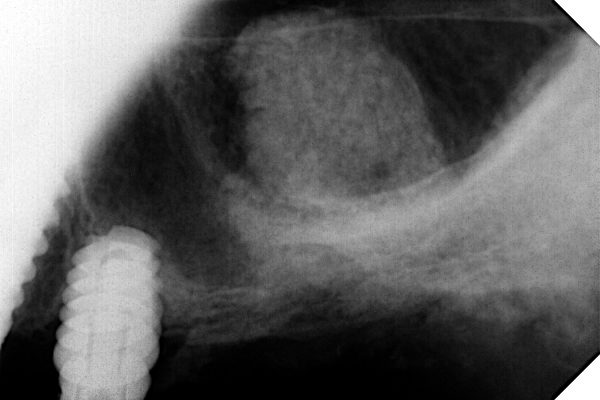

And with kit B (indication more than 4 mm of sub sinus bone with implant placement).